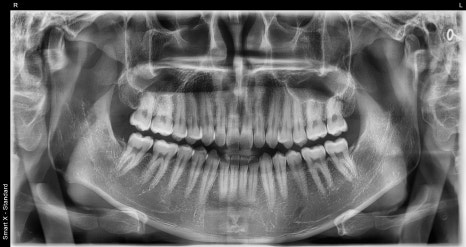

시술 전 사진

오브제로 시술 전 사진